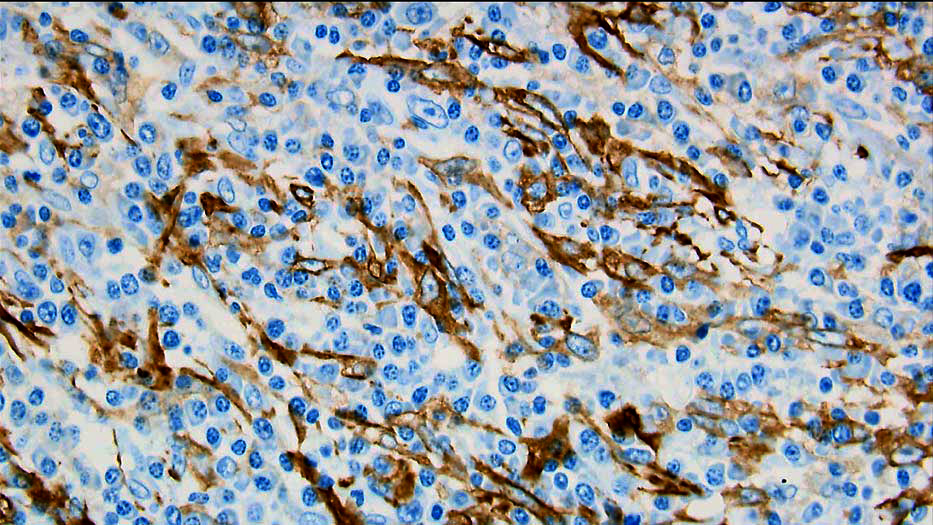

α-SMA免疫染色 |

紡錘形細胞のIgG4発現の検討,濾胞樹状細胞の免疫組織化学的検討の必要性についてコメントあり.形質細胞の異型は炎症性偽腫瘍で説明しうるのかとのコメントあり.また,膵炎の既往と本病変の関連の有無についての質問あり. |